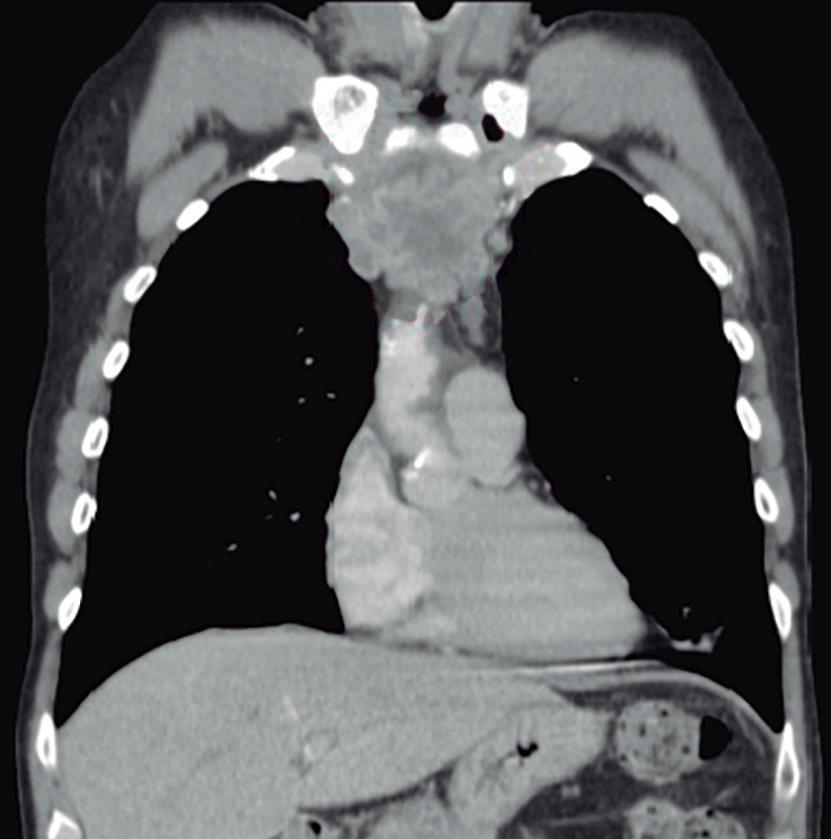

Evaluación de un paciente con dolor epigástrico y hallazgos sincrónicos infrecuentes

Roy López Grove, Daniela Soloaga, Juan Carlos Spina

Roy López Grove, Daniela Soloaga, Juan Carlos Spina 398